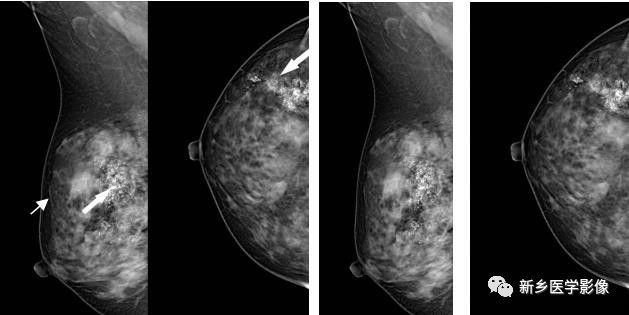

乳腺恶性肿块X线图像

左乳MLO位片示,肿块边缘分叶状,见长短不一毛刺,局部皮肤凹陷(白箭)

左乳MLO位片示,肿块分叶状边缘,周围见透明晕(白箭)

乳腺癌的MRI增强图像

左乳MRI矢状位,呈边缘环状强化向中心渗透,呈向心样强化(白箭)